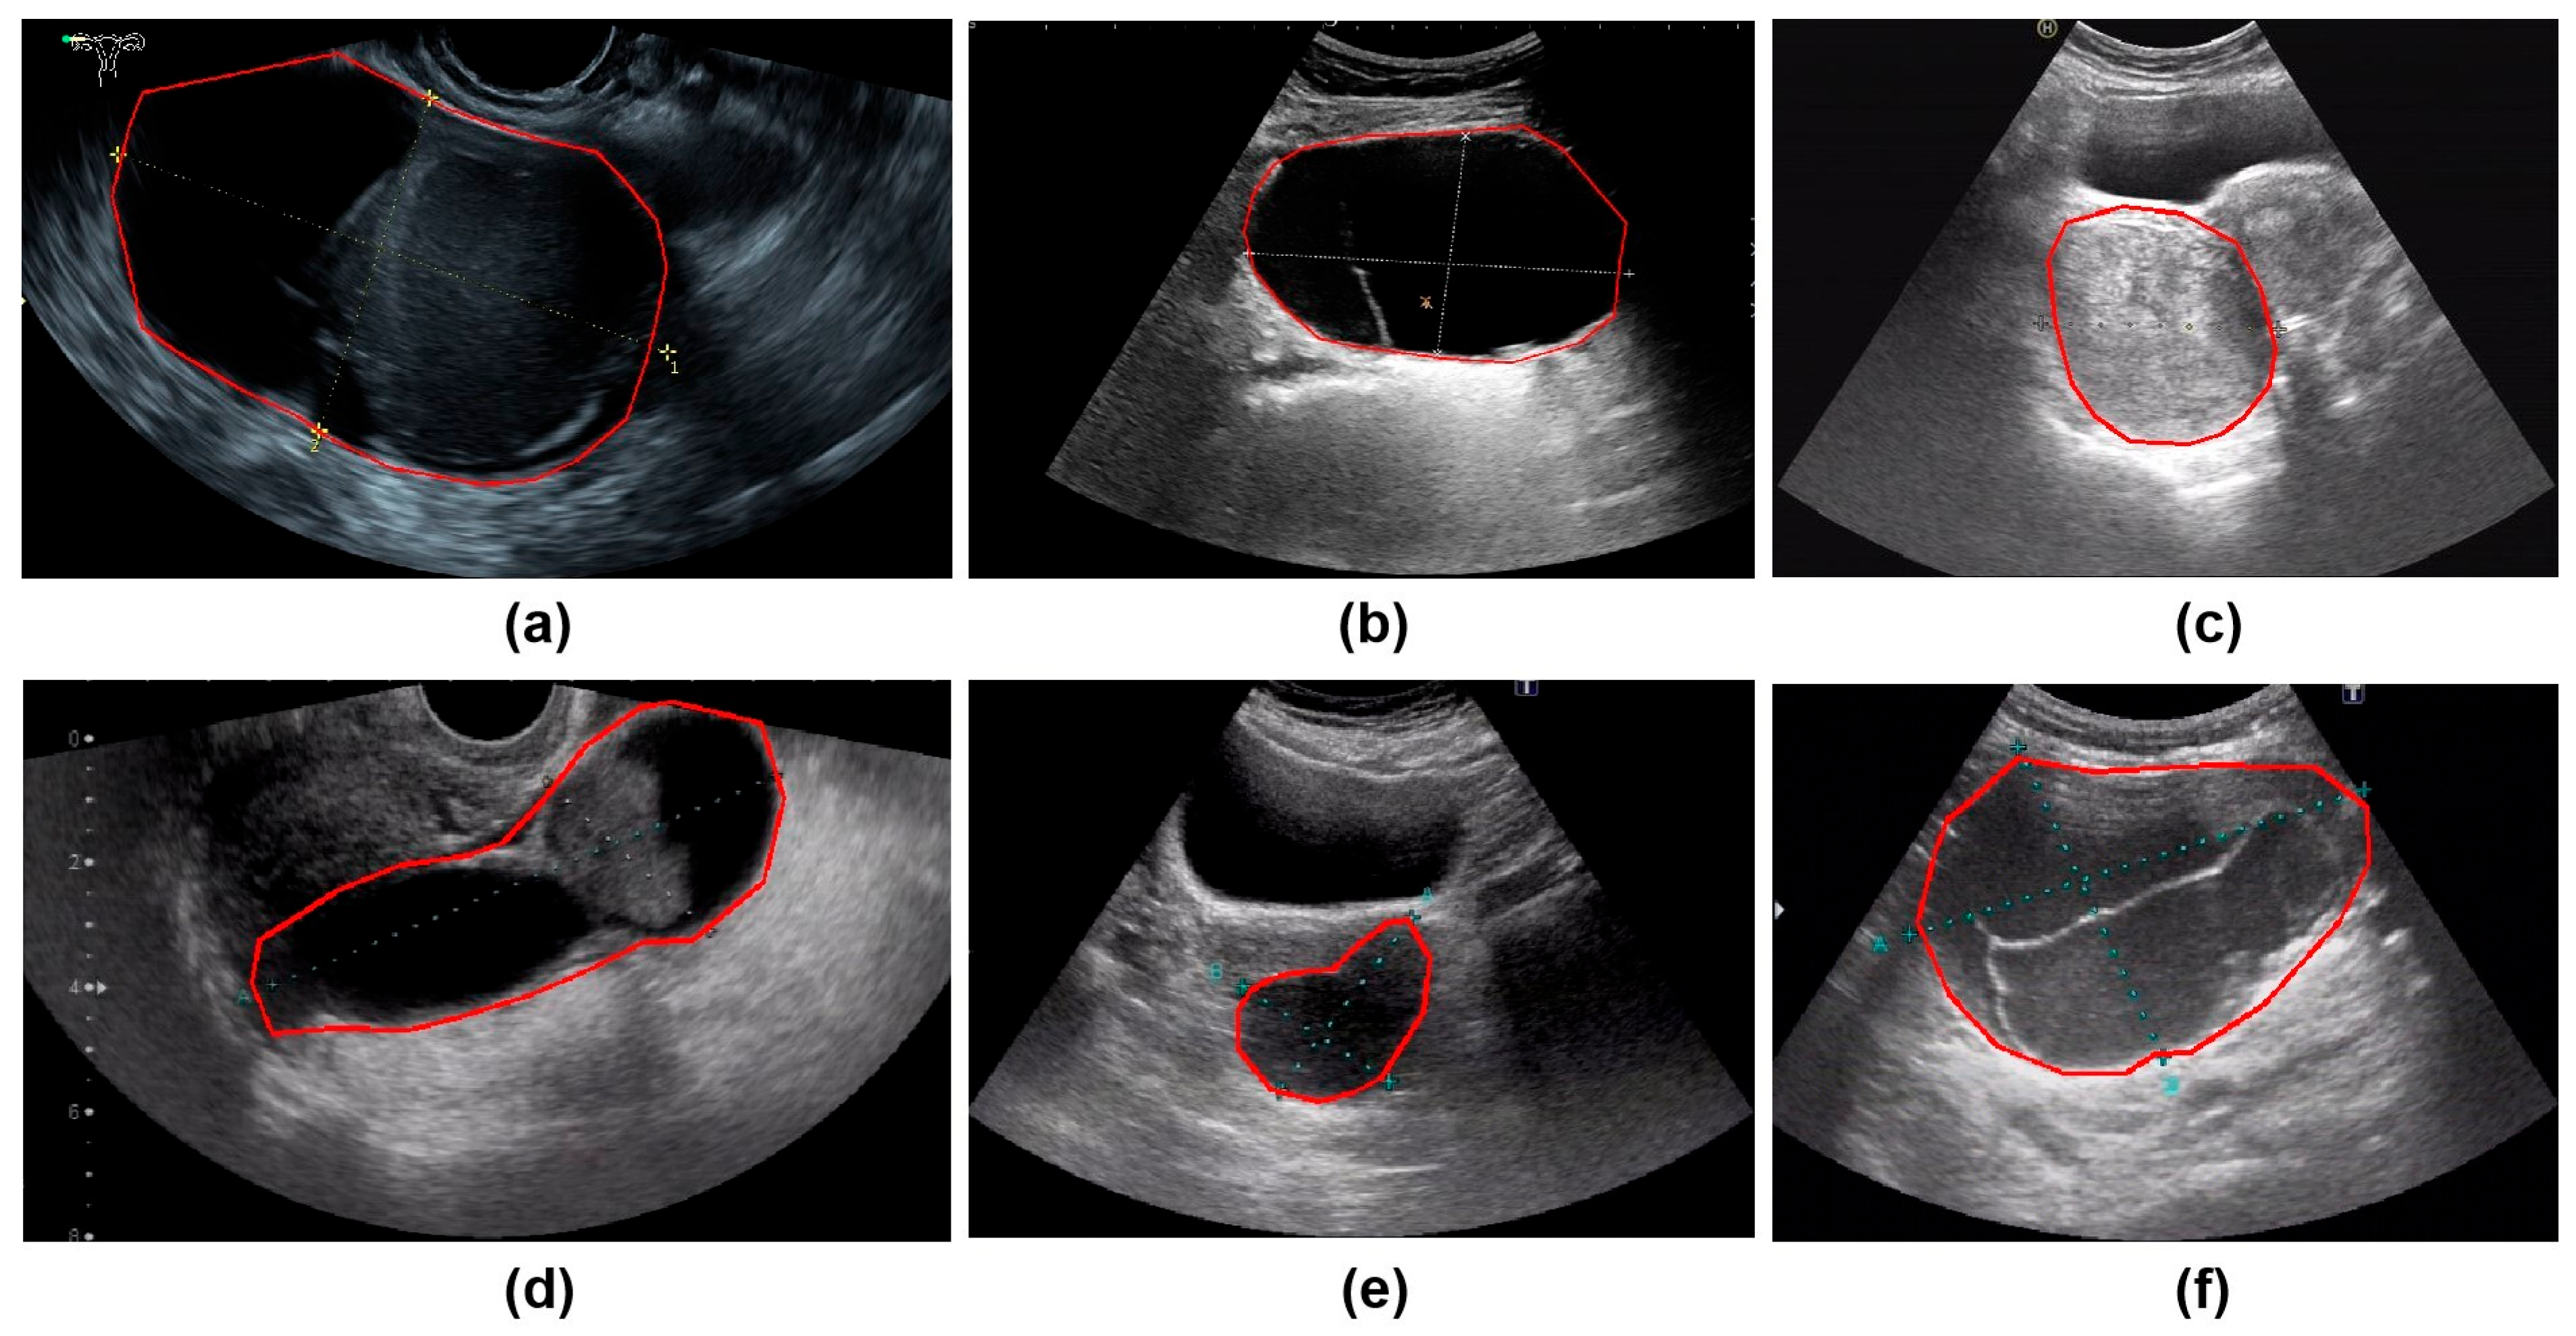

All ultrasound images were obtained from the Picture Archiving and Communication Systems (PACS). Images were acquired using abdominal probes with a frequency range of 1–6 MHz and transvaginal probes with a frequency range of 2–9 MHz. For each patient, the images representing the largest lesion diameter and most complex morphology were selected. Figure 2 provides representative examples of selected cases from this study. Senior radiologists precisely annotated tumor location and boundaries using the Labelme tool (Version 4.5.9, Cambridge, MA, USA) [18]. The lesion regions were then manually cropped and saved as separate images, which were converted to grayscale to standardize the input format for model training.

Figure 2.

The parts circled in red in the image represent the lesions we labelled. (a) A 42-year-old patient with a serous cystadenoma. (b) A 35-year-old patient with a mature cystic teratoma. (c) A 48-year-old patient with a borderline mucinous tumor. (d) A 52-year-old patient with high-grade serous adenocarcinoma. (e) A 65-year-old patient diagnosed with an ovarian fibroma; (f) A 48-year-old patient with an adult-type granulosa cell tumor.